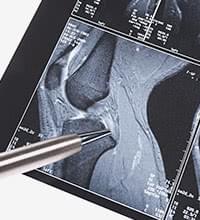

実際の症例2

-

- 年齢・性別

- 20代・男性

- お悩み

- 高校時代、ハンドボールのプレー中にひざを痛め、過去に前十字靭帯と半月板の手術を行っている。若いので、痛みの原因をきちんと治しておきたいとの理由で来院。

- 画像所見

- 外側の半月板は残っているが、内側の半月板は無くなっている。このことから切除手術を受けたことが見て取れる。やや骨の変形が認められることから、変形性膝関節症と考えられる。

- 診断

- 変形性膝関節症